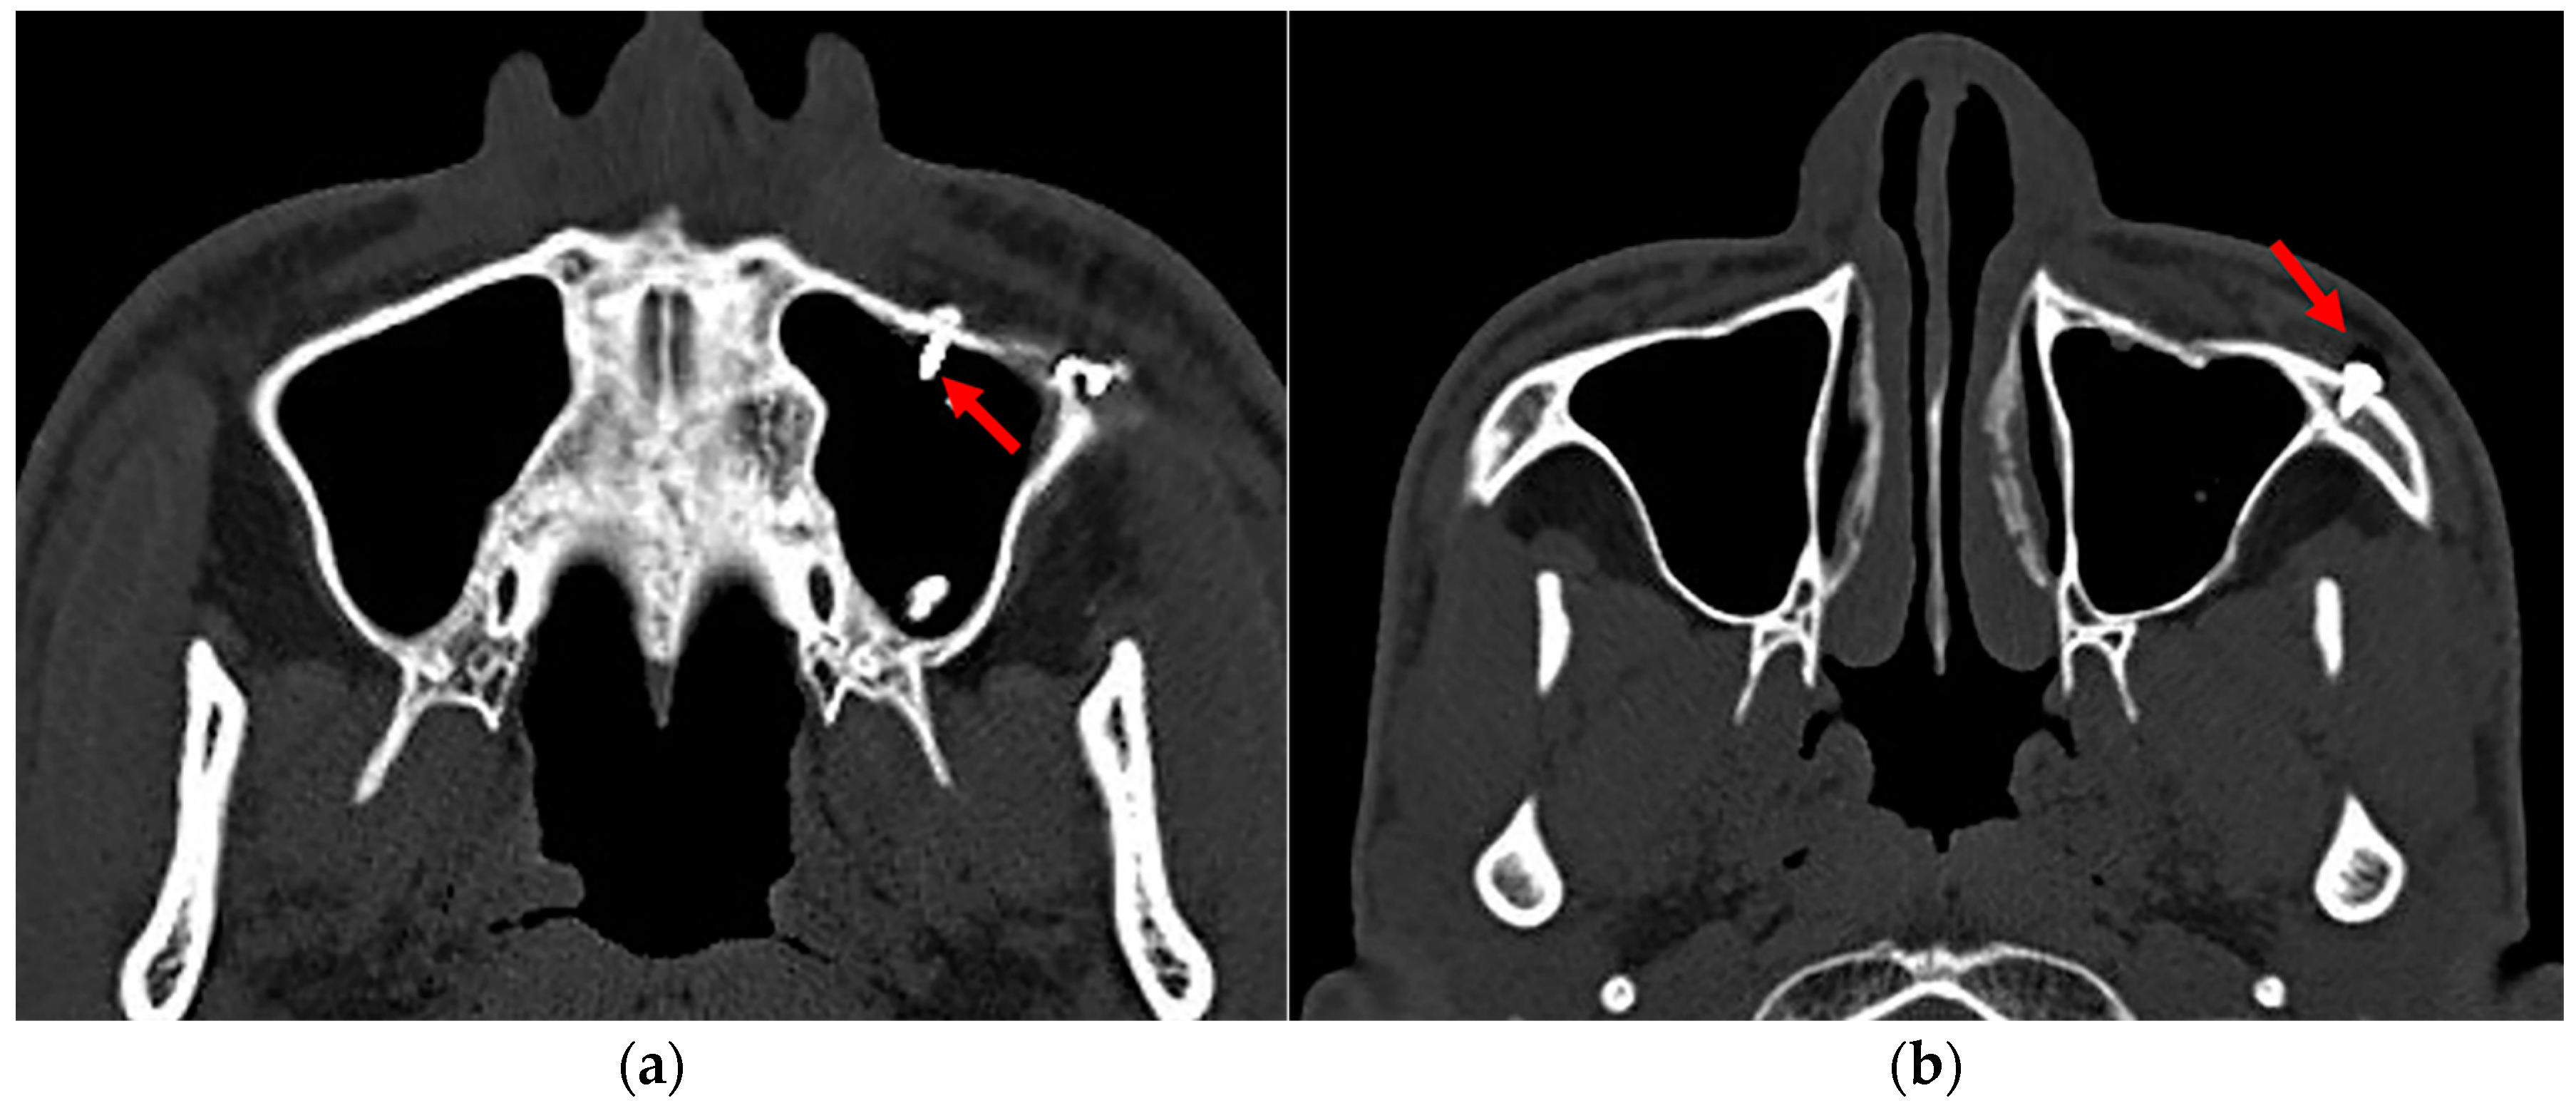

Considering the medial and posterior walls of the maxillary sinus were unapproachable and inaccessible during ORIF, the screws implanted in the anterior wall, superior wall, and floor were counted as the number of screws implanted in the maxillary sinus wall. And once these screws penetrated through the bone wall of the maxillary sinus, they were counted as the number of screws penetrating the maxillary sinus (Figure 2).

Figure 2.

Implant penetration into the maxillary sinus. (a) The arrow indicates the implants (screws) penetrated the maxillary sinus. (b) The arrow indicates the implants (screws) within the maxillary sinus wall.